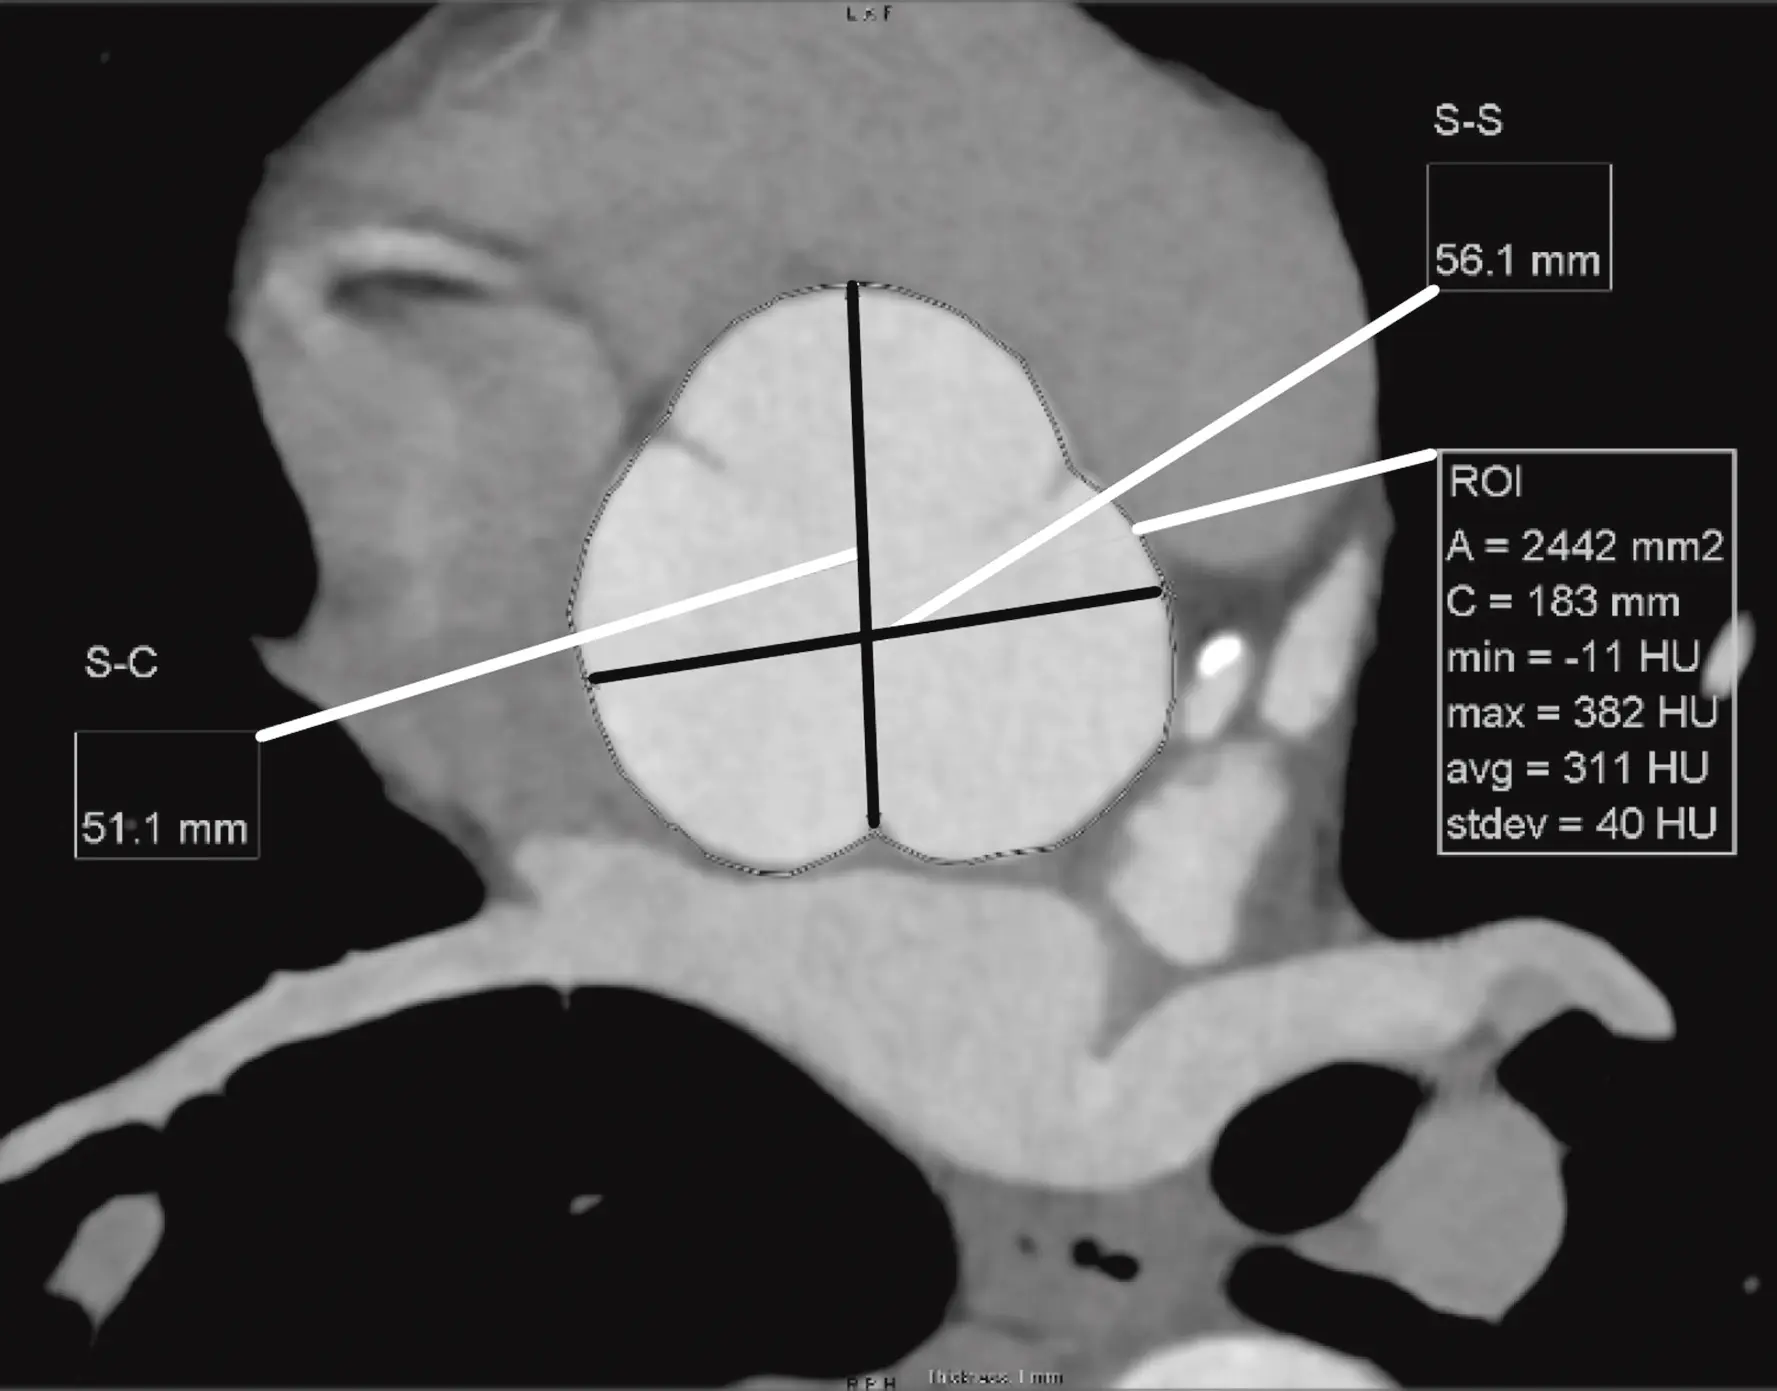

Measure at sinuses of Valsalva

- Measure aortic root diameter at the sinuses of Valsalva on CT

- Drag the lines until you see the widest section in the coronal and sagittal planes

- Now in your axial view (SAX), you will measure commissure to sinus.

- You can also measure from sinus-to-sinus

Sinus-to-sinus versus sinus-to-commissure1

Figure source: 2